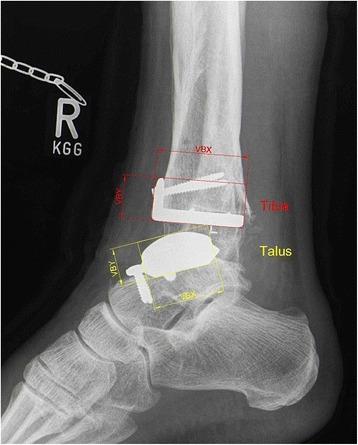

The rotational position of the leg substantially influences measurements in ankle radiographs after total ankle replacement (TAR). The aim of our study was to further specify the influence of different projections on radiographic parameters used to assess component position after TAR.

The effect of varying degrees of internal rotation, flexion, and ab-/adduction on reference lines in anteroposterior and lateral ankle radiographs was investigated in a cadaveric TAR model. Observed variations were then compared with those found in 34 consecutive patients that received a HINTEGRA total ankle prosthesis in our department.

A change of rotation of 20° resulted in a variation of measured reference lines of more than 1.3 cm in anteroposterior radiographs and more than 1 cm in lateral radiographs in our experimental setting. Even higher intraindividual changes of up to 1.4 cm were observed in our in vivo series.